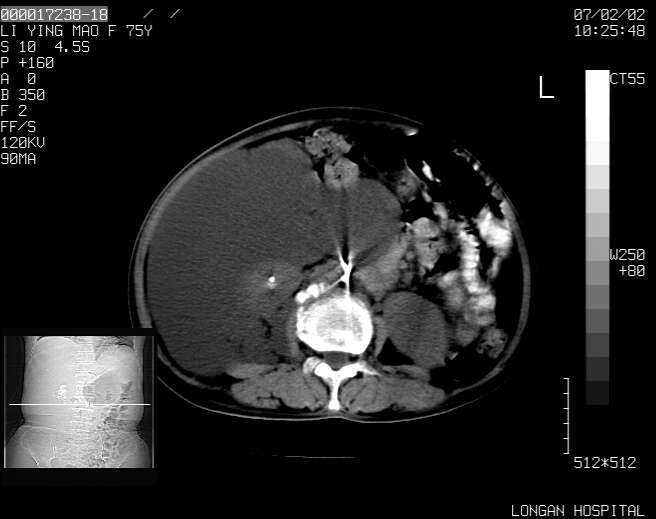

以下是引用dyqct在2007-2-10 8:53:00的发言:[br]考虑:1、肝脏多发囊肿[br] 2、左肾囊肿,右肾多发结石并积水。[br] 3、右胸少量积液。[br] 4、右肾周包裹性积液或淋巴管瘤(有见缝就钻的征象、薄隔、小结节状钙化)?[br] 5、腰椎动脉瘤样骨囊肿?[br] [br] [br]